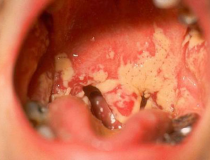

Bình thường chúng ta đều biết đến bệnh lậu ở bộ phận sinh dục và lầm tưởng rằng bệnh lý này chỉ xuất hiện ở cơ quan sinh dục nhưng ít ai biết được vi khuẩn lậu còn có thể xuất...